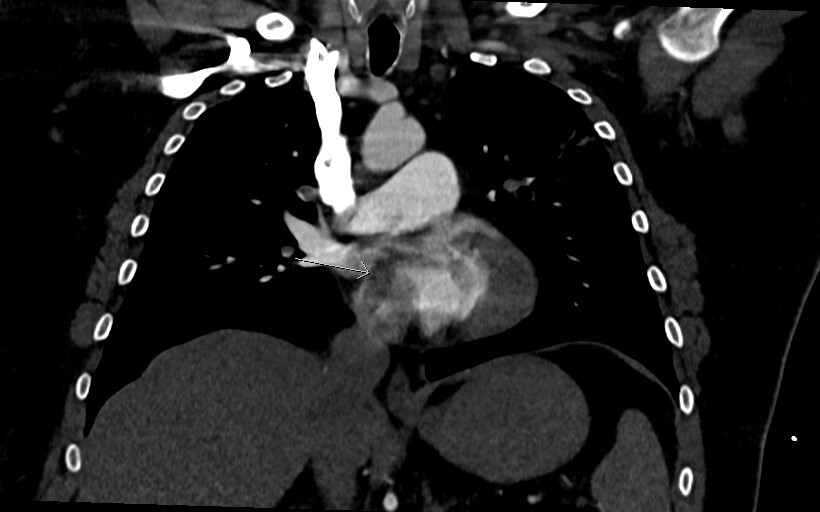

Figure 2 is an axial slice which shows a well-defined, round, homogenous and low attenuation filling defect (long white arrow) in the right atrium (RA) positioned adjacent to the interatrial septum (IAS). The filling defect is visible in the RA even despite the contrast mixing artefact in the RA chamber, the aforementioned features indicated the presence of a structure within the RA chamber, in this instance thrombus.

Figure 3 is the axial slice below and shows an elongated low attenuation and homogenous structure extending across a defect in the IAS into the left atrium (short arrow) and when viewed in contiguous slices was inseparable from the RA filling defect. This represented intracardiac thrombus in transit (ICTIT). There were further low attenuation, homogenous and well defined filling defects (medium white arrow) in the left atrium (LA). The radiologist also noted that the right heart chambers were enlarged compared to the left, and that both the IAS and interventricular septum (IVS) were inversely bowed toward the left – these are CTPA features that can indicate elevated right heart pressures and therefore right heart strain in the clinical context of PE.